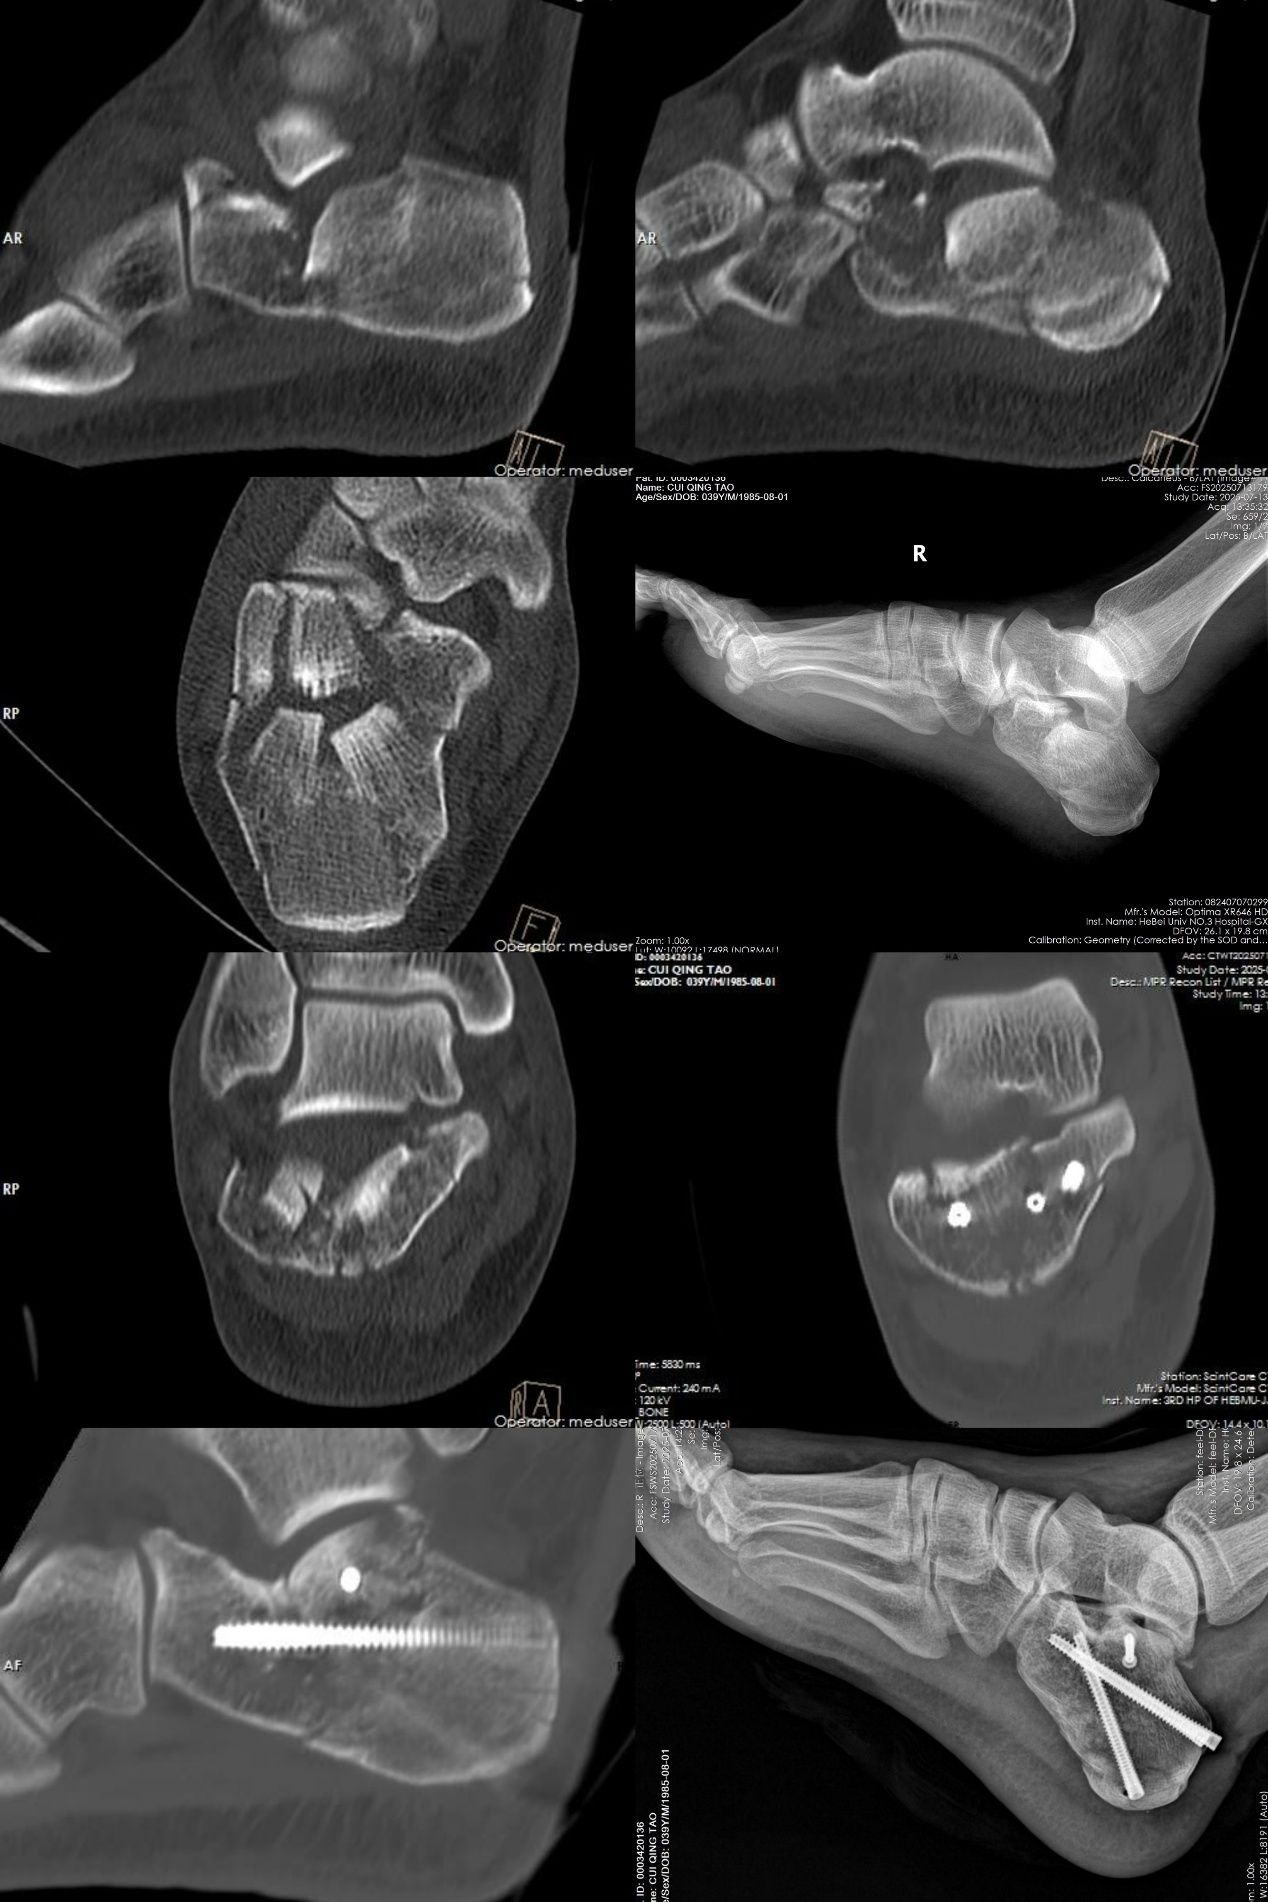

该项微创手术具有多项显著优点。首先,手术无需传统大切口。医生仅通过体表几个如“钥匙孔”般的微小穿刺点,借助特殊器械与术中实时影像引导,在闭合状态下实现骨折块的精准对位,恢复跟骨原有结构。复位后采用经皮植入螺钉完成固定,最大限度保留软组织完整性,使患者可更早开展康复训练。

其次,该手术可降低软组织损伤及相关并发症。手术过程中对肌肉、韧带、血管及神经的影响较小,从而显著减少术后感染、皮肤坏死、伤口愈合不良等常见风险。患者不再需要为并发症过度担忧,康复过程更加顺畅安心。

不仅如此,由于手术创伤小,患者术后疼痛感也明显减轻,可以更早开始踝关节功能锻炼与系统康复。“早活动”是促进骨折愈合、避免关节僵硬、提升功能恢复效果的关键。微创手术让患者能更快、更主动地投入康复训练,整体恢复周期大幅缩短,回归日常生活的速度也明显加快。